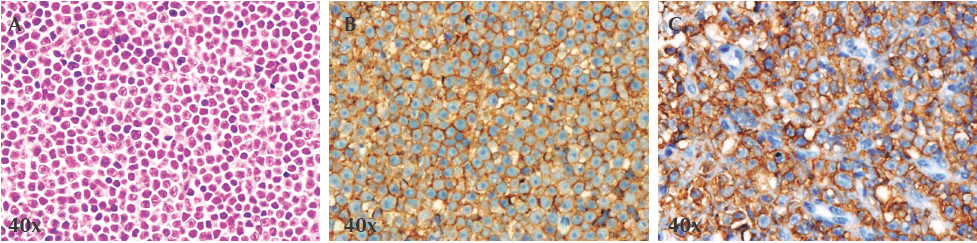

Actualmente no existe un esquema terapéutico ideal para población pediátrica. Los informes de casos en adultos han mostrado supervivencia a largo plazo sólo con quimioterapia. La serie pediátrica más grande sugiere que la mayoría podría lograr remisión a largo plazo sólo con quimioterapia, sin radioterapia craneoespinal; No obstante, dichos estudios son limitados debido a que las series de pacientes eran muy pequeñas4,5,16,17,19 (Cuadro 1). El pronóstico es pobre, se ha informado supervivencia libre de eventos a 5 años desde 25 hasta 40%; entre la población pediátrica dicha supervivencia es de hasta 70% pero con una tasa alta de recaídas.1,2,4,5,15-17

En nuestra investigación sólo encontramos tres series pequeñas de pacientes en edad pediátrica4,5,15 que mencionan buena respuesta al tratamiento y alcanzaron supervivencia de más de 70% (Cuadro 1); pero la población incluida, la metodología y los tratamientos utilizados fueron diversos y su comparación difícil.